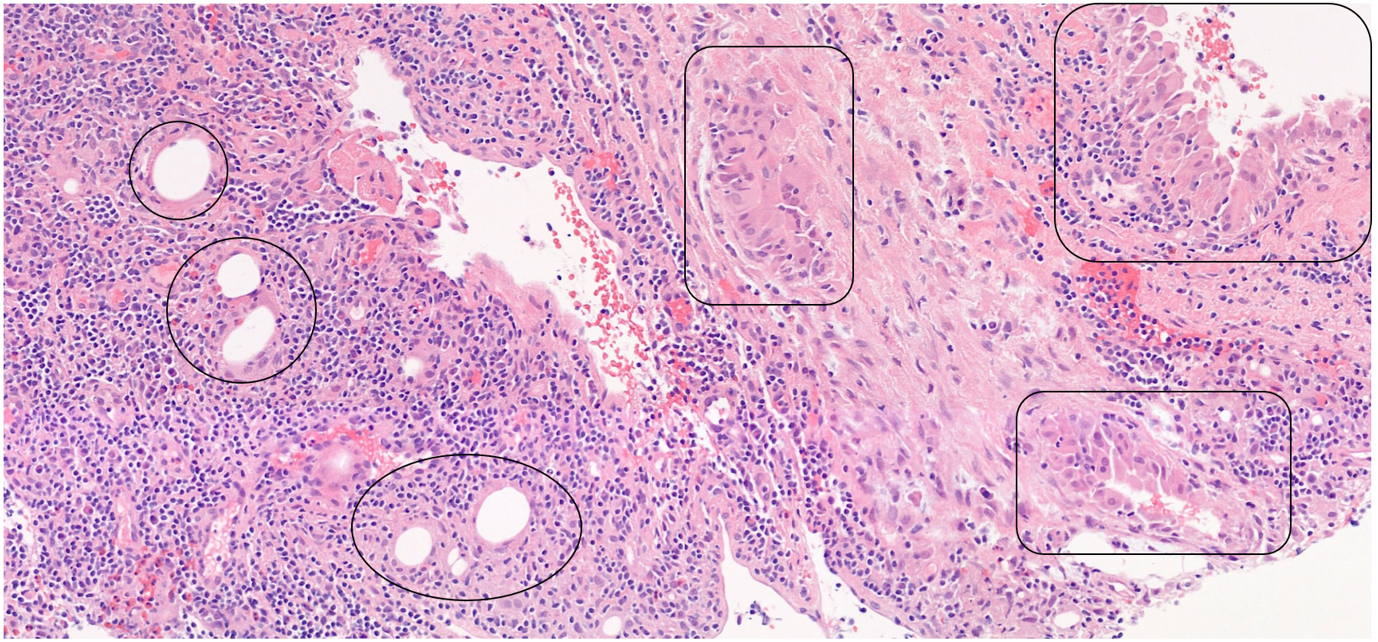

结果:腋窝淋巴结脂肪浸润。

9a209bfa122b6920704aa5ad2f09a5f5.pngd959577af5abcb3b584853407685a39d.png

至今尚无研究报告显示腋窝淋巴结在自体脂肪移植(AFT)后出现脂肪浸润。然而,我们的病例通过病理学确认了这一现象。影像学发现显示这些脂肪沉积在 T1 加权 MRI 图像上表现为小的脂肪衰减区域,而在超声检查中则表现为脂肪回声。

研究表明,腋窝淋巴途径是乳腺组织的主要引流途径,淋巴液直接引导或通过Sappey丛的网络运输到腋窝。在不同情况下都观察到了细胞或颗粒通过淋巴通道的迁移,这表明通过自体脂肪移植引入的脂肪细胞可能会沿着这些既定的淋巴通路移动。这为脂肪及其吞噬细胞沉积在腋窝淋巴结中的存在提供了一个合理的机制,这一点得到了我们的影像学和病理学的证实。